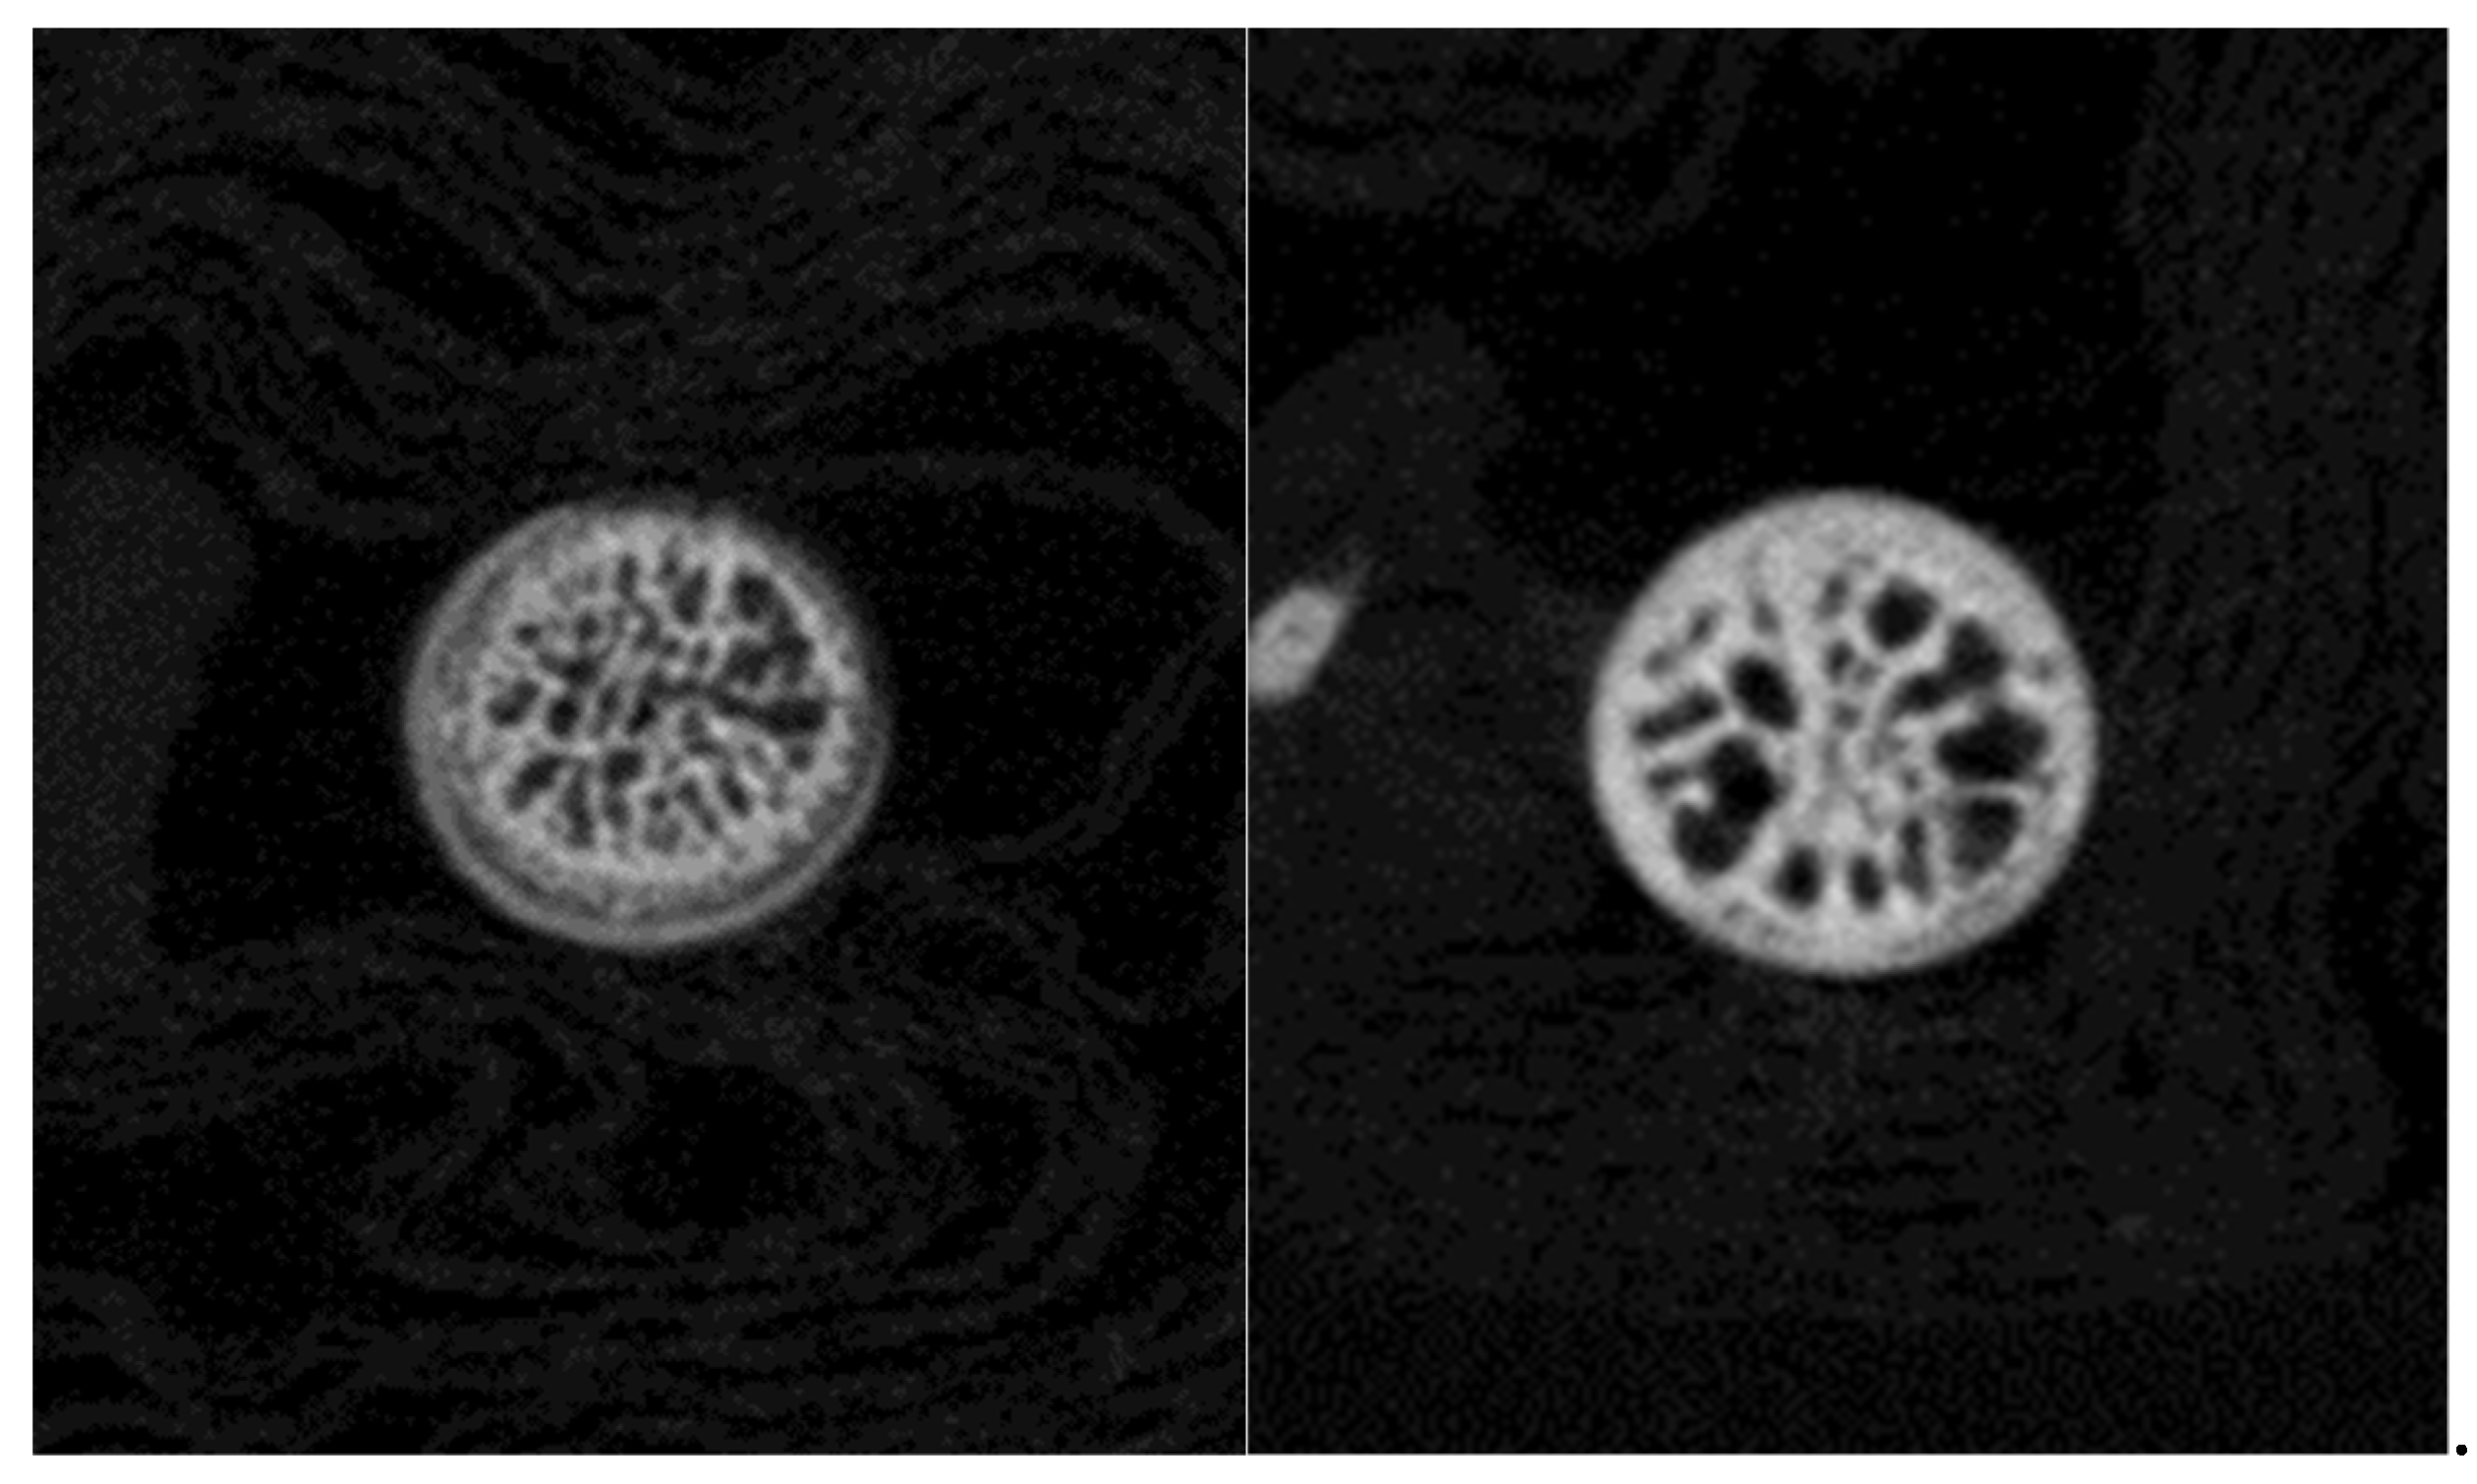

The quality of femur bone, lumbar vertebra, and hip joint of aging mice was evaluated in the present study. Male and female mice of a wide range of ages (7 to 80 weeks), strain Black6, were scanned using X-ray microtomography. Parameters such as mineral density were calculated to assess bone quality.

The parameter values and the images recorded reveal that bony and cartilage tissues remain in healthy condition until the age of 1 year. From this point, decay takes place in bone (osteoporosis) and joints (osteoarthritis). Mineral density of femur and vertebra trabecular bone decreases, while the free space between bone rods increases. The spongy architecture is maintained with wider gaps. The trabecular bone becomes less (Figure 1).

The cartilage covering the femoral head in hip joints mineralizes. It converts to a thick bony layer, losing the elastic properties of the chondral tissue (Figure 2). Osteoarthritis is installed. On the other hand, subchondral bone remains dense until the age of 80 weeks.

Figure 1.

X-ray microtomographic section of a 7 weeks (left) and 80 weeks (right) lumbar vertebra. Trabecular bone is declining.